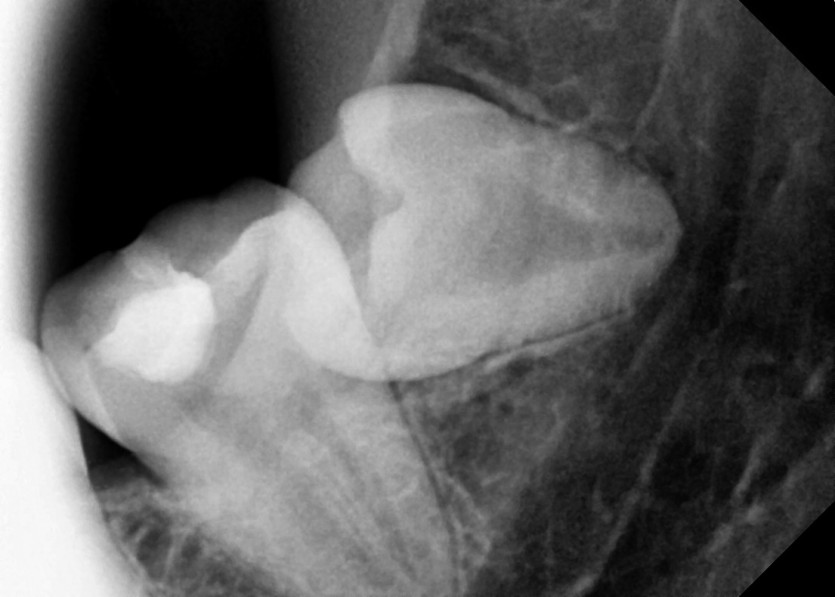

#18,28,38,48 사랑니 발치

구강 외과 전문의가 당일 발치했습니다.